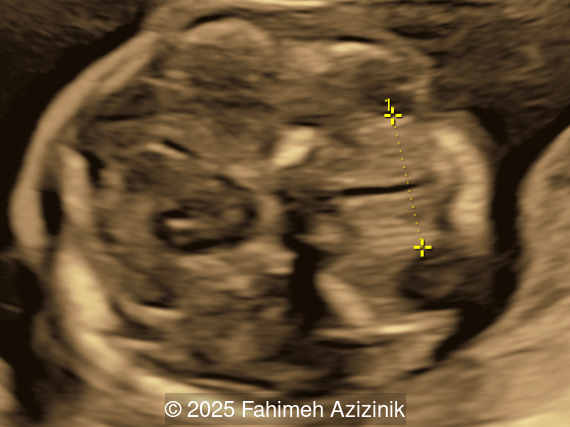

Image 1

• Complex syndactyly of the hands and feet. Complex hand brachysyndactyly with “mitten-like” appearance due to bony fusion of the fingers

• Bicoronal craniosynostosis

• Hypertelorism

• Frontal bossing

Bicoronal synostosis is the characteristic cranial hallmark of Apert syndrome, detectable sonographically from 18 weeks. Its most recognizable manifestation is turribrachycephaly, defined by an elevated cephalic index (typically >85–90%) and a tall cranial vault with marked frontal bossing [19]. On prenatal ultrasound, the face in Apert syndrome shows midface hypoplasia with a depressed nasal bridge, proptosis, hypertelorism, and frontal bossing. The extremities demonstrate syndactyly of both bone and soft tissue of the hands and feet with partial-to-complete fusion often involving second, third, and fourth digits, known as “mitten hands” and “socked feet”. In severe cases, all digits are fused, with the presence of a single nail known as “synonychia” [20]. Other ultrasound findings include mild ventriculomegaly, agenesis of the corpus callosum, deficient or absent septum pellucidum, and fusion of the cervical vertebrae at the level of C5-C6 [21]. Cardiovascular (atrial and ventricular septal defect) and genitourinary anomalies (hydronephrosis, and cryptorchidia) are present in 10% of patients [22]. Increased nuchal translucency in the first trimester [23], widely open metopic suture [24], and polyhydramnios [25] have also been reported. Three-dimensional (3D) ultrasound facilitates assessment of surface abnormalities of the face and extremities, and magnetic resonance imaging (MRI) can be used to evaluate associated intracranial conditions [26].